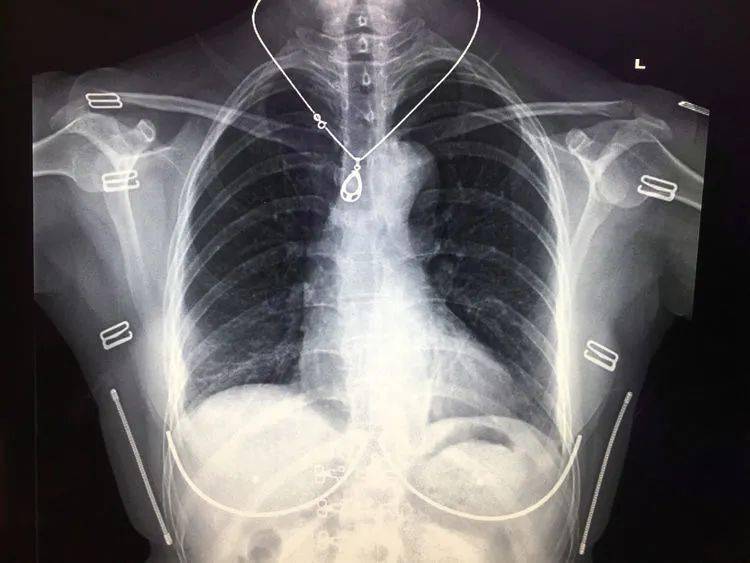

文章图片

存在体表金属异物的胸部正位平片 , 图片来自镇安县医院影像科

部分女性内衣以及带金属的拉链、金属扣的衣物都会影响拍摄效果 , 拍摄前医生会要求尽量把这类衣物脱掉 。

首饰类如金属项链、玉石挂件也需要摘掉 。